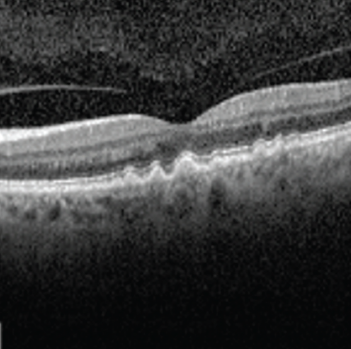

Il arrive parfois que de petits arbres poussent à travers les fissures du trottoir. Ils peuvent écarter les bords du trottoir et causer beaucoup de dégâts en peu de temps. C’est ce qui arrive à l’œil dans le cas de la DMLA humide. Des vaisseaux sanguins peuvent commencer à se développer dans des zones affaiblies sous la rétine externe. Ces vaisseaux laissent fuir du liquide et du sang, ce qui provoque des gonflements et des cicatrices, qui entraînent une perte de vision. Parce que les dommages qu’elle cause surviennent relativement vite, la DMLA humide provoque une perte de vision plus soudaine comparativement à la DMLA sèche.

Dans le cas de la DMLA humide, une protéine appelée facteur de croissance de l’endothélium vasculaire (VEGF) favorise la croissance de vaisseaux sanguins anormaux sous la macula. Ces vaisseaux sanguins peuvent laisser fuir du liquide et du sang, formant ainsi un tissu cicatriciel sous la rétine, ce qui entraîne une perte de vision permanente. La bonne nouvelle est que nous disposons de médicaments appelés anti-VEGF qui ciblent ces vaisseaux sanguins anormaux. Les anti-VEGF freinent la croissance et la fuite des vaisseaux sanguins et provoquent le rétrécissement et la disparition des vaisseaux sanguins anormaux, empêchant ainsi toute perte de vision supplémentaire. À mesure que le liquide autour de ces vaisseaux sèche, les symptômes de perte de vision peuvent même s’atténuer.